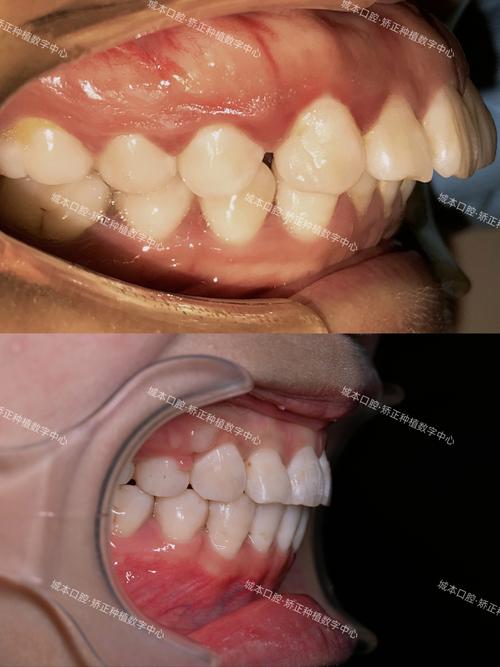

牙齿与上颌骨的关系密不可分:牙齿的牙根深埋于牙槽骨中,而牙槽骨属于上颌骨的一部分,当牙齿存在前突(如“龅牙”)或排列拥挤时,上颌骨可能会因牙齿的异常力量而出现轻微前移或形态代偿性改变,上前牙过度前突时,上颌骨的前部可能随之向前突出,导致鼻骨的基底位置相对靠前,鼻梁与面部的夹角减小,视觉上鼻梁显得“塌”或不够立体。

正畸治疗通过内收前突的牙齿(如使用拔牙矫正、隐形矫正的“推磨牙向后”等技术),减少上前牙对上颌骨前部的牵引力,随着牙齿逐渐向舌侧移动,上颌骨可能发生轻微的逆时针旋转(即前部略微后移、后部略微上抬),这一变化会改变鼻骨基底的倾斜角度,当鼻骨基底位置相对后移且角度更垂直时,鼻梁在视觉上会显得更挺拔,高度“增加”,这种变化并非鼻骨本身变长或变高,而是鼻骨与面部其他骨骼的相对位置调整带来的轮廓优化。